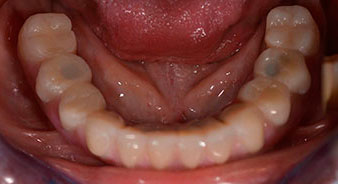

A three-dimensional cone beam computed tomography scan (CBCT, Planmeca) was performed to aid planning and minimize risks. This revealed that the quality and quantity of the available bone were sufficient for the surgery and immediate restoration using the Fast & Fixed method. Following the protocol for this concept, the implants are inserted at 35, 32, 42 and 45. Angling the distal implants by up to 45° shifts the emergence profile to posterior and generates a larger support polygon (Fig. 3).

Angled abutments (35°) were screwed in to compensate for the divergence of the distal implants, with the result that the emergence profile of all implants was as perpendicular as possible to the bite plane. This is a prerequisite for occlusal placement of the provisional and subsequently the permanent denture (Fig. 15 and 16).

The impression and bite registration were then performed so that the dental technician could begin producing the provisional restoration immediately. This was then screwed in on the same day (Fig. 17 and 18).